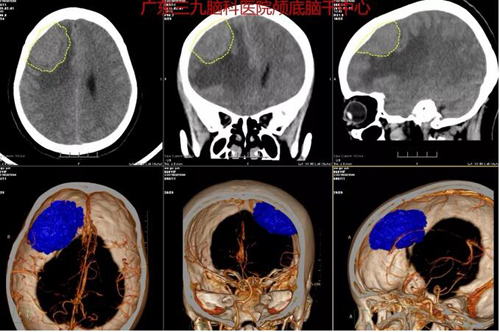

图1:术前CTA示右侧额部占位性变病,其内血管供血丰富,临近血管受压呈弧形